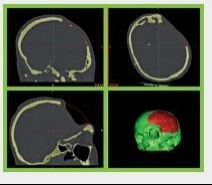

Základní popis Výroba speciálních zakázkových implantátů využívaných pro neurochirurgii, kranioplastiku, korekci vad velkých kostí, maxilofaciální chirurgii a plastickou chirurgii

Indikace

* zejména po autonehodách a onkologické léčbě

Materiály